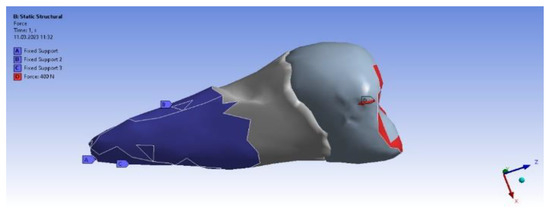

3. Finite Element Analysis (FEA) of Mandibular Right Premolars